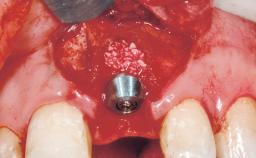

Late Placement of an Implant in a Maxillary Left Central Incisor Site

Bone Augmentation Horizontal|Staged

Placement Protocol Early or late implant placement

Bone Volume Deficient horizontally, requiring prior grafting